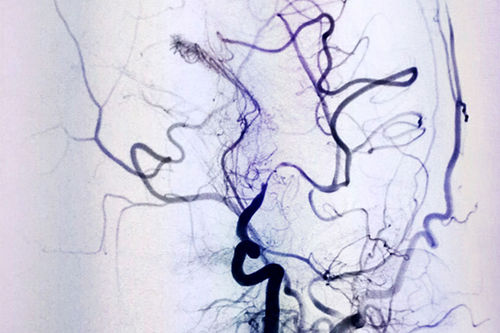

DSA血管造影,仿佛医生绘出的生命图腾

DSA血管介入诊断和治疗,像一种“血管艺术”,初看如水墨丹青一样的术中影像图,如同医护人员用智慧和技巧绘制的生命图谱。上海蓝十字脑科医院DSA血管介入诊疗是医院特色科室,拥有非常完善和先进的设备,李振并主任已经使用DSA成功诊断和治疗了很多大面积脑梗患者。